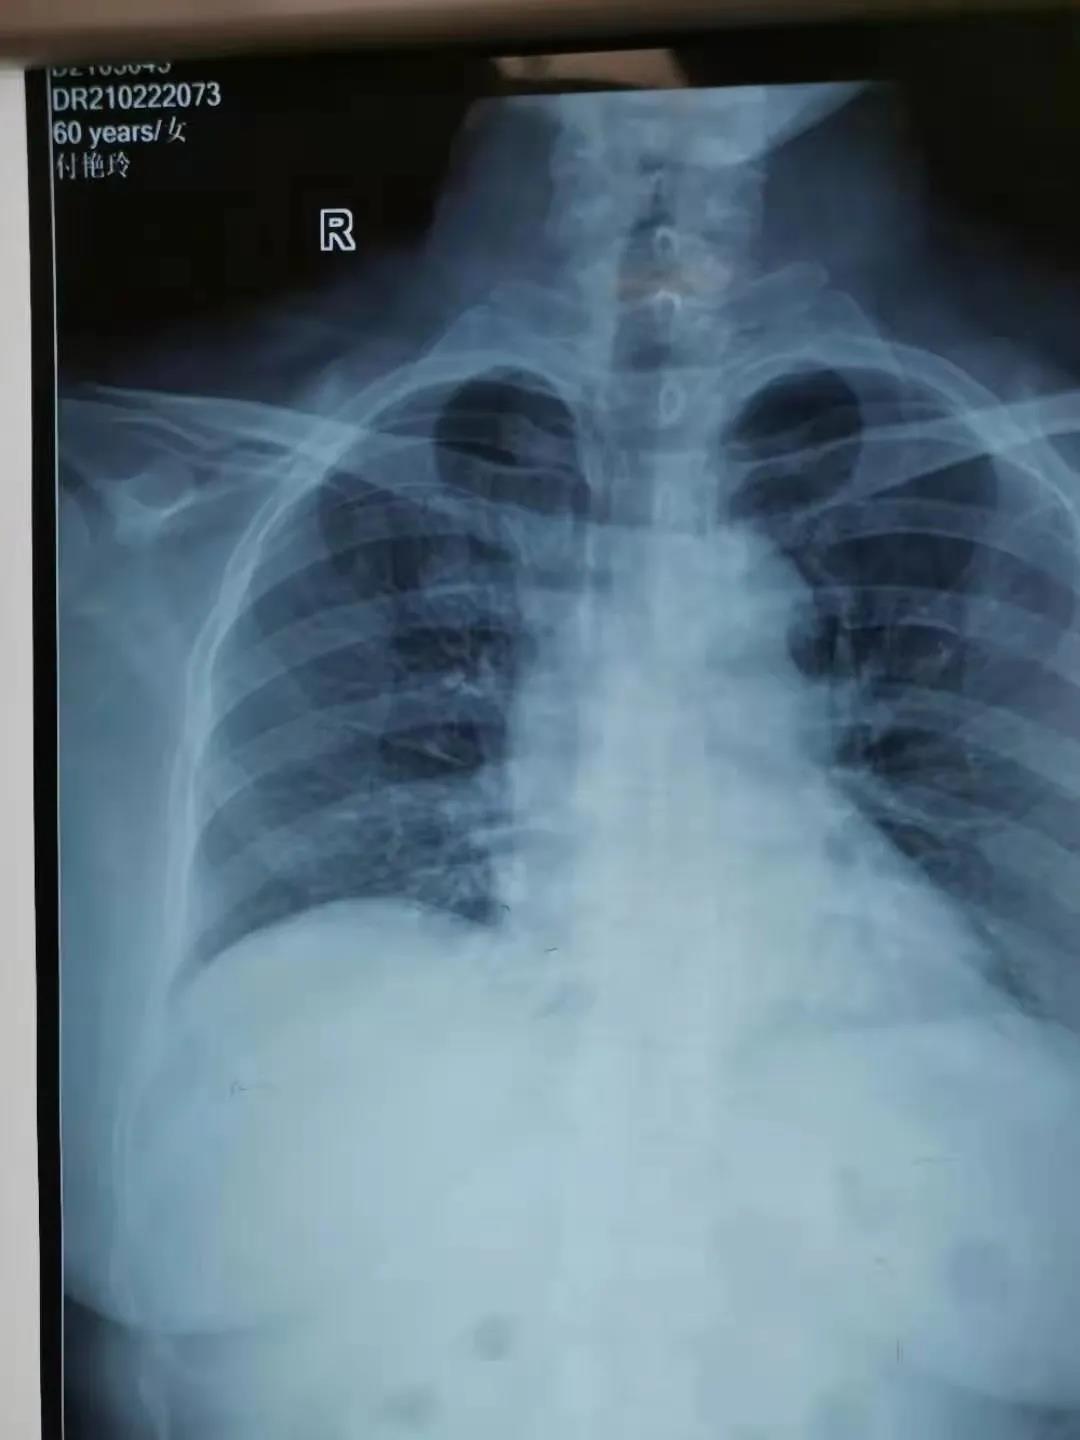

2月22日,由鄲城縣第二醫療健康服務集團鄲城縣中醫院腫瘤血液科護士長劉曉娟,護士丁星文、馬慧、張玉霞成立的靜脈治療專科小組,在經過了數例PICC置管中進行心電腔內(ECG)定位與x線下定位結果的比較后成功運用了ECG定位技術置管,此項技術的成功開展,標志著醫院PICC置管定位技術又上新臺階!

ECG腔內定位技術是一種在置管過程將特殊的心電導聯線聯接導管導絲和心電圖機,在送入導管過程中通過觀察心電圖上P波的特征性變化來判斷導管尖端的位置的方法,此項技術實現了在術中實時定位和調整導管頭端,達到精準定位PICC導管頭端位置的目的。

ECG定位技術通過一“進”兩“退”的方式(一進:當導管尖端到達CAJ時,可見高尖P波,進入右心房后P波雙向,由高尖再轉低;一退:當導管尖端從右心房退回上腔靜脈時P波恢復正常。再退:導管繼續后退2-3 cm到達最終正確的位置。)判斷導管尖端位置,及時糾正導管異位、極大的提高了導管尖端位置定位的準確性,避免了因反復調整導管位置所致的并發癥(靜脈炎、導管相關感染、血栓等)及因導管異位而重復拍片,保證了患者安全,提高了工作效率。③7